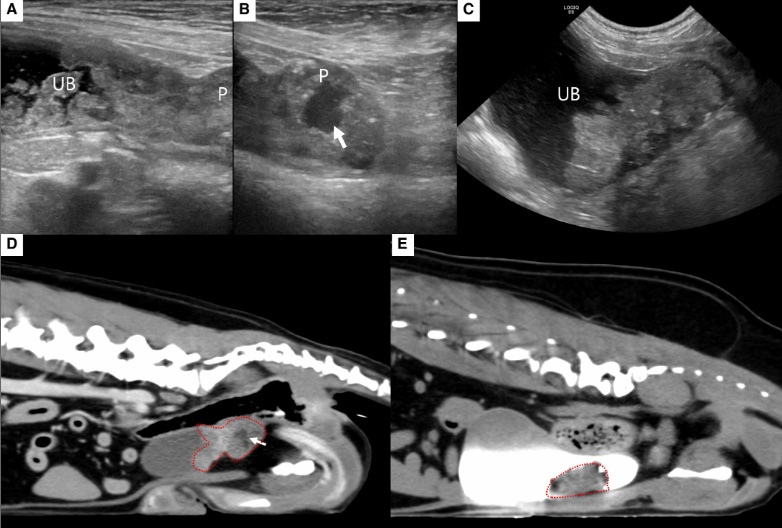

그러면서 면역매개성 사구체신염(ICGN), 변비, 요독증, CKD 관련 미네랄골질환(Mineral Bone Disorder) 등 삶의 질에 영향을 미치는 합병증의 진단과 치료 전략을 소개했다.